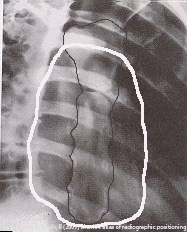

Why is RAO preferred for sternum imaging?

Places sternum over heart shadow, reducing lung/rib superimposition.

How much rotation is used for RAO sternum?

15–20° (15° hypersthenic, 20° asthenic).

Where is the CR directed for RAO sternum?

At T7, 2.5 cm left of midline.

What breathing technique helps visualize the sternum?

Shallow breathing with low mA and long exposure (2–4 sec).

What does under-rotation look like in RAO sternum?

Sternum still superimposes spine.

What does over-rotation look like in RAO sternum?

Sternum lateral to heart shadow, foreshortened.